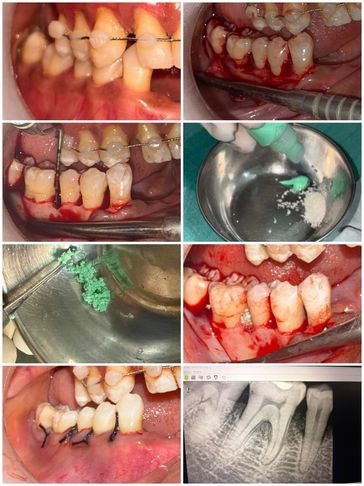

Zoledronate (zoledronic acid) gel along with bone grafts can be used in surgical therapy for treating intrabony defects. As a third-generation nitrogen-containing bisphosphonate, it exhibits the highest antiresorptive potency among available bisphosphonates, making it particularly effective for modulating alveolar bone density.